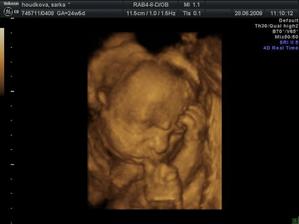

27.3 09 vyšetření screening dopdl dobře 🙂 miminko je zdravé má 11+5tt a 8cm žádná vývojová vada se nenašla. Jen placenta má rýhy jizvičky od hematomů,ale to prý nevadí to se zahojí.Hematomy už jsou pryč 🙂 28.5 Vyšetření a velký ultrazvuk ve 21tt dopadl dobře miminko zdravé vše bylo v pořádku , ukázal nám že to je kluk jako buk a váží už 413g .Také ve 21tt dává o sobě vědět už to není jen bublání v bříšku,ale semtam kopaneček a to tak dvakrát za den 🙂 4D ultrazvuk ve 25tt

Už jseme ve 31tt kontrola u doktora na jedničku Fanda už váží 1788g prý je krásné miminko 🙂 tak jsem pyšná 🙂 od 3O tt se Fanda už krásně převaluje ,ale mám malé bříško a Fanda má prý malo místa na řádění takže nemám veliké bolestivé kopance,ale jen převalovaní a je to moc příjemný je to mazlík,když začnu hladit bříško začně mi rust boule na břiše jak se tiskne k ruce..to si užíáváme každý den 🙂